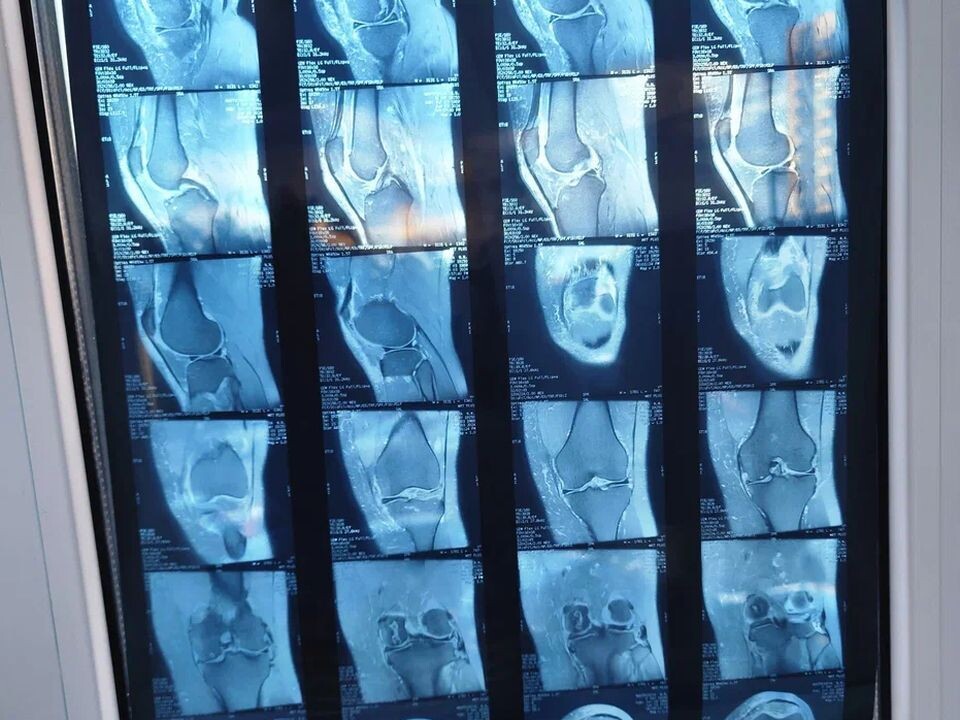

• При артрозе: главный метод — рентген или МРТ. На снимках будет четко видно сужение суставной щели и изменения в хряще.